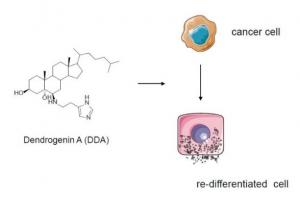

CANCER: Découverte d'un suppresseur de tumeur puissant et prometteur